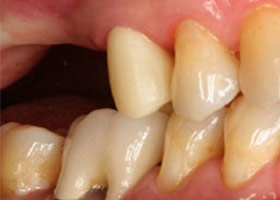

最後裝置假牙

完成照片